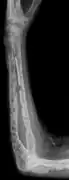

The diagnostic examination of a person with suspected multiple myeloma typically includes a skeletal survey. This is a series of X-rays of the skull, axial skeleton, and proximal long bones. Myeloma activity sometimes appears as "lytic lesions" (with local disappearance of normal bone due to resorption). And on the skull X-ray as "punched-out lesions" (pepper-pot skull). Lesions may also be sclerotic, which is seen as radiodense.[48] Overall, the radiodensity of myeloma is between −30 and 120 Hounsfield units (HU).[49] Magnetic resonance imaging is more sensitive than simple X-rays in the detection of lytic lesions, and may supersede a skeletal survey, especially when vertebral disease is suspected. Occasionally, a CT scan is performed to measure the size of soft-tissue plasmacytomas. Bone scans are typically not of any additional value in the workup of people with myeloma (no new bone formation; lytic lesions not well visualized on bone scan).

-

X-ray of the forearm, with lytic lesions -

Multiple myeloma in the upper arm -